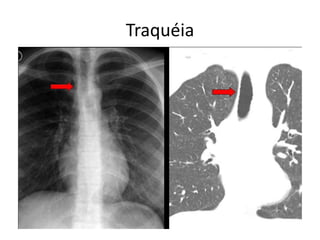

Traquéia